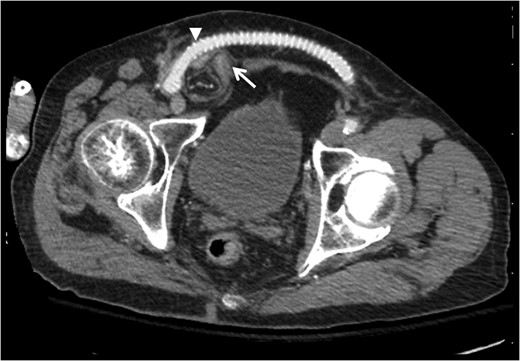

Contrast-enhanced computed tomography axial image demonstrating relationship of bowel-containing inguinal hernia (arrow) with femorofemoral PTFE graft compressing the area of the internal ring (arrowhead).